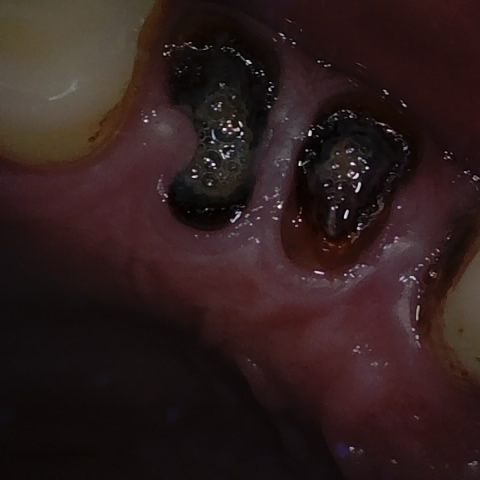

Annotated as "Good"